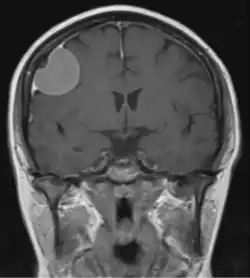

Dural tail sign

The dural tail sign (also known as dural thickening, the flare sign, or the meningeal sign) is a radiological finding observed in magnetic resonance imaging (MRI) studies of the brain that refers to a thickening of the dura mater immediately adjacent to a mass lesion, such as a brain tumor.[1] Initially, the dural tail sign was thought to be pathognomonic of meningioma, a slow-growing tumor that arises from the meninges.[1] However, subsequent studies have shown that it can also be observed in various intra- and extra-cranial pathologies and in spinal lesions.[1] It is not a completely sensitive finding, as it is seen in only 60-72% of cases.[2] It is not completely specific either, as it has been described associated with lesions like neuromas, chloromas, pituitary diseases, granulomatous disorders, cerebral Erdheim-Chester disease, lymphomas, metastasis, hemangiopericytomas, schwannomas, and gliomas such as glioblastoma multiforme (GBM).[2][3] The final diagnosis should be further established through cerebrospinal fluid analysis or histopathological examination following a biopsy.[3]

The dural tail sign was first described in 1989 by Wilms et al..[1][4] Histopathological correlation from different studies has at times revealed tumor infiltration into the dura mater, however, in most instances, it signifies a hypervascular, non-neoplastic response.[3]